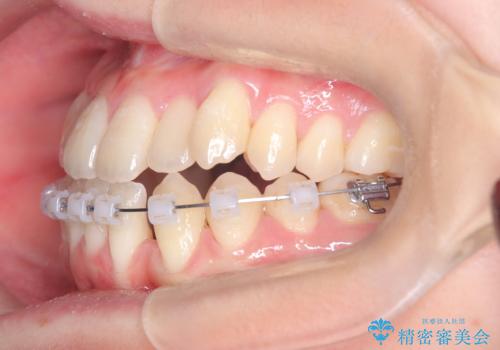

安全かつ確実に抜歯スペースを閉じ、咬み合わせを完成させるため、マウスピースから**ワイヤー矯正(マルチブラケット装置)**へ切り替えるリカバリープランを提案しました。

装置の変更と歯肉への配慮: ワイヤー矯正は歯の根(歯根)を平行に移動させる「歯体移動」を得意としています。本症例では、歯肉退縮を防ぐために、歯の傾きを精密にコントロールしながら抜歯スペースを閉じる必要がありました。ワイヤー装置を用いることで、インビザラインでは難しくなっていた三次元的な細かい調整を可能にしました。

リカバリーのプロセス: 適合が悪くなったインビザラインを一旦中止し、ブラケットを装着。停滞していた歯の移動を再開させ、上下の正中(中心)や奥歯の咬み合わせを一つひとつ整えていきました。